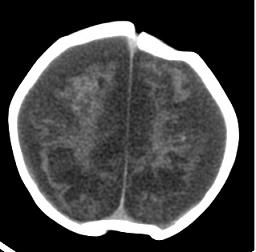

男,4个月大,2个月前无诱因下四肢抽搐、伴呕吐,近2天来抽搐频发,伴发热。查体:双眼疑视,神萎、纳差;颈抵抗,四肢张力高。

病史太长了,原因不好定,不过如果2个月前小儿正常的话可考虑积水型无脑畸形,积水型无脑畸形小儿刚生下来表现可正常,存活一两个月后出现症状.

另不除外缺血缺氧性脑病,感染等改变

2个月前缺血缺氧性脑病留下的后遗症。

脑出血后,软化灶形成了。脑发育不良

支持缺血缺氧性脑病留下的后遗改变(脑软化灶+脑发育不全+双侧慢性硬膜下积液+小头畸形)。

要注意化脓性脑膜、脑炎,硬膜下积脓,脑积水的可能,建议腰穿助诊。